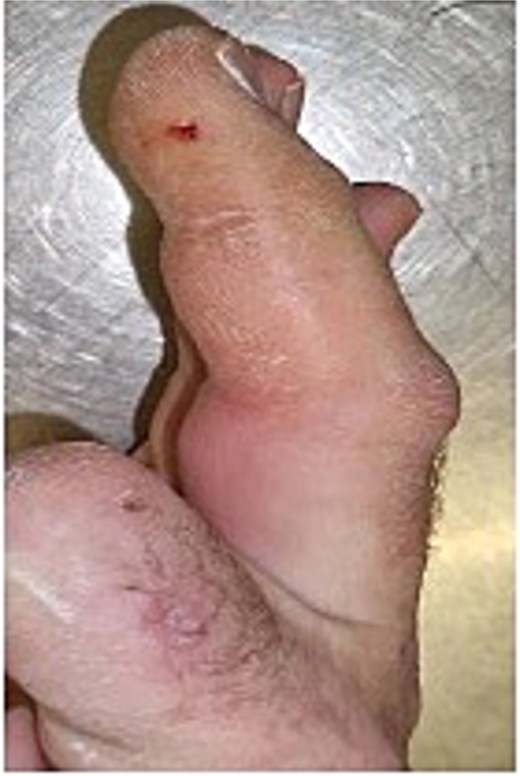

Initial presentation (Fig. 4) with accompanying X-ray (Fig. 5) and intra op image during first debridement (Fig. 6).

Image of patient two, showing his digit at presentation displaying very small puncture wound on lateral volar surface of his digit.

X-ray image of patient two showing injected material into volar surface of his digit.